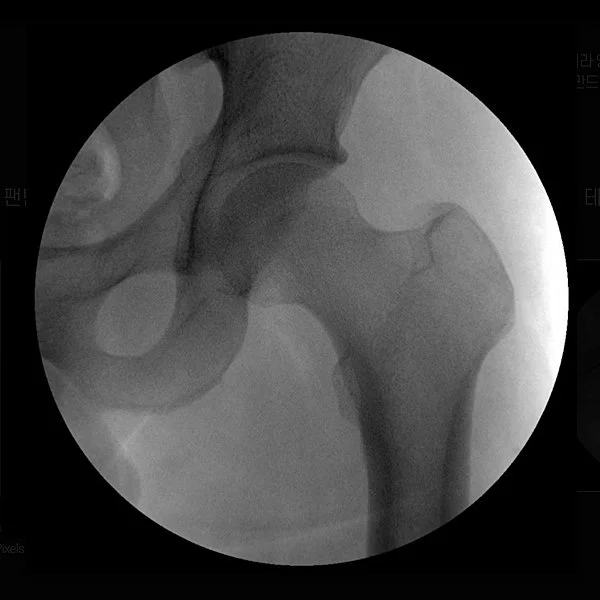

Take 23. Hip Joint without Filter

Take 23. Hip Joint with Filter